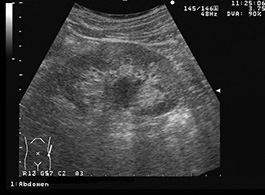

肉眼的血尿の精査目的で検査した症例。腎盂拡張が軽度あり、腎盂の中には淡いエコーレベルの低い充実性エコーが見られる。本例では腫瘍自体は不明瞭だが、腎盂の部分的な拡張は腎盂癌を発見する糸口となる。